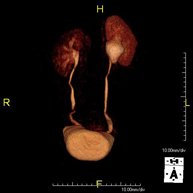

Prova diagnòstica no invasiva que consisteix en l'obtenció d'imatges d'alta definició anatòmica de tot el cos mitjançant l'ús d'un camp electromagnètic i ones de ràdio (amb un emissor i un receptor). No utilitza radiació ionitzant. És una prova molt important en la recerca de metàstasi en pacients amb neoplàsia coneguda. No requereix preparació prèvia. No és necessari l'ús de contrast paramagnètic (Gadolini). - Angio-RM d'Aorta abdominal

Prova diagnòstica no invasiva que consisteix en l'obtenció d'imatges d'alta definició anatòmica de tot el cos mitjançant l'ús d'un camp electromagnètic i ones de ràdio (amb un emissor i un receptor). No utilitza radiació ionitzant. És una prova molt important en la recerca de metàstasi en pacients amb neoplàsia coneguda. No requereix preparació prèvia. No és necessari l'ús de contrast paramagnètic (Gadolini). - Angio RM d'Aorta-ilíaca

Prova diagnòstica no invasiva que consisteix en l'estudi de l'artèria aorta abdominal i de les artèries ilíaques, amb l'obtenció d'imatges d'alta definició anatòmica mitjançant l'ús d'un camp electromagnètic i ones de ràdio (amb un emissor i un receptor). És indispensable l'ús de contrast paramagnètic (Gadolini). No utilitza radiació ionitzant. La qualitat de les imatges permet realitzar reconstruccions en 2D i 3D. Aquesta prova està especialment indicada com a estudi prequirúrgic (mapa vascular) abans d'intervencions percutànies o quirúrgiques d'aorta abdominal i artèries ilíaques, per a l'estudi complementari en pacients amb isquèmia de membres inferiors, etc. - Angio RM Arterial d'extremitats inferiors

Prova diagnòstica no invasiva que consisteix en l'estudi de l'artèria aorta abdominal per obtenir imatges d'alta definició anatòmica mitjançant l'ús d'un camp electromagnètic i ones de ràdio (amb un emissor i un receptor). És indispensable l'ús de contrast intravenós paramagnètic (Gadolini). No obstant, no utilitza radiació ionitzant. La qualitat de les imatges permet realitzar reconstruccions en 2D i 3D. Està indicat en aquells pacients amb malaltia vascular (Aterosclerosi), per a l'estudi d'aneurismes, en estudis prequirúrgics de lesions adjacents a l'aorta abdominal com "mapa" vascular, etc. - Angio-RM Aorta ilíaca

Prova diagnòstica no invasiva que consisteix en l'estudi de l'artèria aorta abdominal per obtenir imatges d'alta definició anatòmica mitjançant l'ús d'un camp electromagnètic i ones de ràdio (amb un emissor i un receptor). És indispensable l'ús de contrast intravenós paramagnètic (Gadolini). No obstant, no utilitza radiació ionitzant. La qualitat de les imatges permet realitzar reconstruccions en 2D i 3D. Aquesta prova està especialment indicada com estudi prequirúrgic (mapa vascular) abans d'intervencions percutànies o quirúrgiques d'aorta abdominal, per a l'estudi complementari en pacients amb isquèmia de membres inferiors, etc. - Angio-RM d'Artèries renals